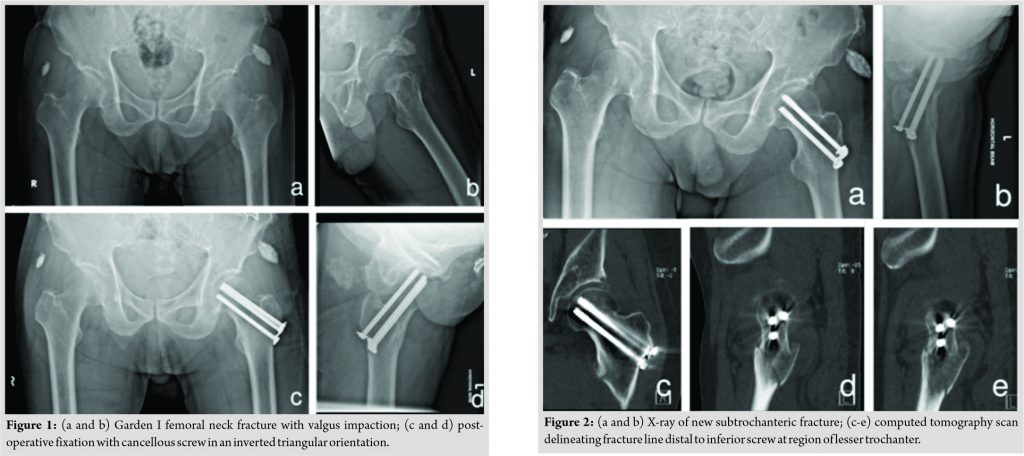

A 73-year-old Chinese male patient, who was a community ambulant without aid, slipped and fell while walking. Radiographs revealed a valgus-impacted NOF fracture (Fig. 1a and b). The patient underwent an uneventful cancellous screw fixation with three7.3mmscrews inserted in an inverted triangular configuration (inferior screw placed midway between the anterior and posterior cortices, superior screws placed as anterior and as posterior as possible in the sagittal plane, in the middle of the femoral neck on anteroposterior [AP]imaging). Threads of all three cancellous screws passed the fracture line into the femoral head (Fig. 1c and d).Post-operative Garden’s alignment index was satisfactory at 160° in the AP plane and 170° in the lateral plane. The patient recovered well postoperatively and regained independent ambulatory status. At 10-month post-operative, the patient sustained another fall while walking and complained of pain over the left hip and inability to weight bear. Radiographs and computed tomography (CT) imaging revealed a peri-implant subtrochanteric fracture with a fracture line originating distal to the inferior screw at the level of the lesser trochanter (Fig. 2a and e).